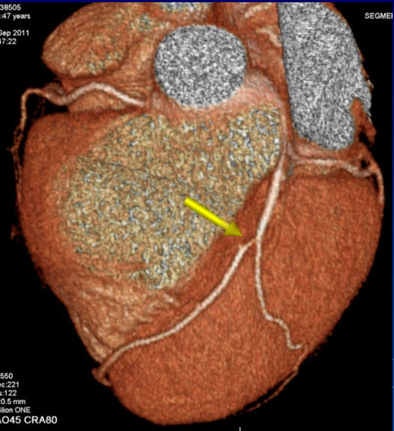

The results showed that 55% of the patients had atherosclerosis, 49% had no significant lesion, and more than 6% had significant lesions (> 70% luminal narrowing), he said. Age, male gender, diabetes, serum cholesterol, smoking, and hypertension were related to the presence of atherosclerosis.

As for major adverse events, there was one sudden death, one myocardial infarction requiring stent implantation, one percutaneous coronary intervention, two cases of unstable angina, and three cases of atypical chest pain -- and all these patients had nonobstructive atherosclerotic plaque at CTA. The results are in line with other data such as the Coronary CT Angiography Evaluation for Clinical Outcomes (CONFIRM) registry, in which patients with a nonobstructive lesion at CTA had higher mortality than patients with no plaque, Hidalgo said.

The patient who died, for example, was a smoker with moderate hypertension who had "a couple of plaques in the proximal [left anterior descending artery], but no significant lesions," he said. The cause of death was unknown, and perhaps not of cardiovascular origin, he added.